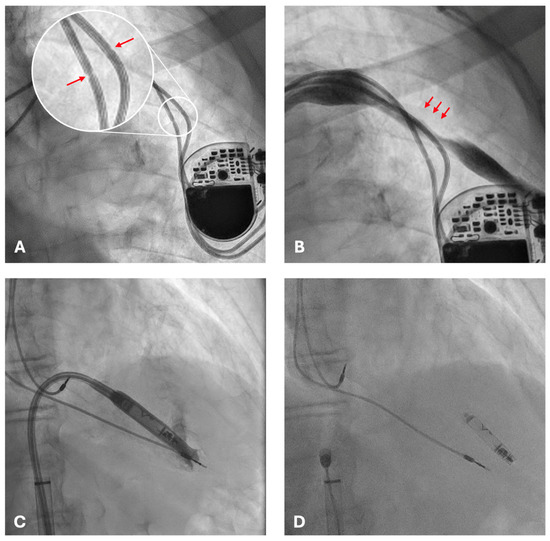

2. Case Presentation